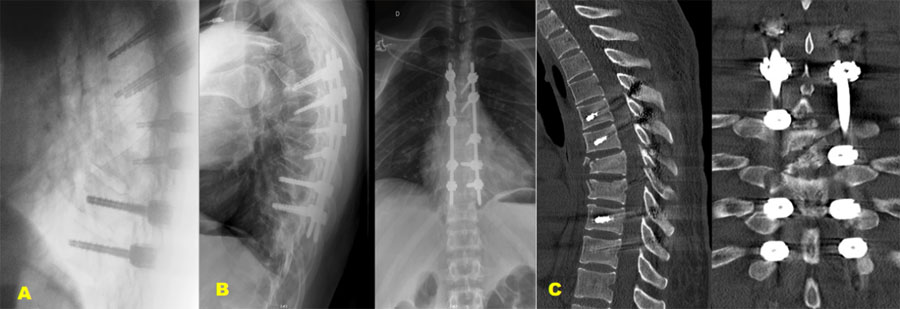

Figure 2. A 28-year-old male patient has a history of recurrent dislocation of the right shoulder, for which he underwent surgery three years ago. He was involved in a traffic accident, colliding with a car while riding his motorcycle and being thrown from it.

Severe pain in his back and left forefoot, as well as deformity and functional weakness in his right shoulder. The patient was neurologically intact and temporary loss of consciousness.

Example case 2: neurologically intact patient